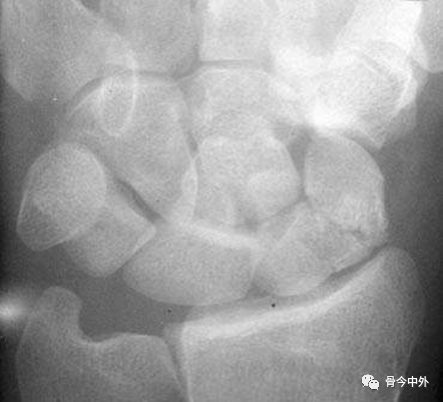

图3 成人期腕关节正侧位及舟骨蝶位片。12.舟骨结节。黑色箭头:舟骨腰部;白色箭头:舟骨滋养血管影。